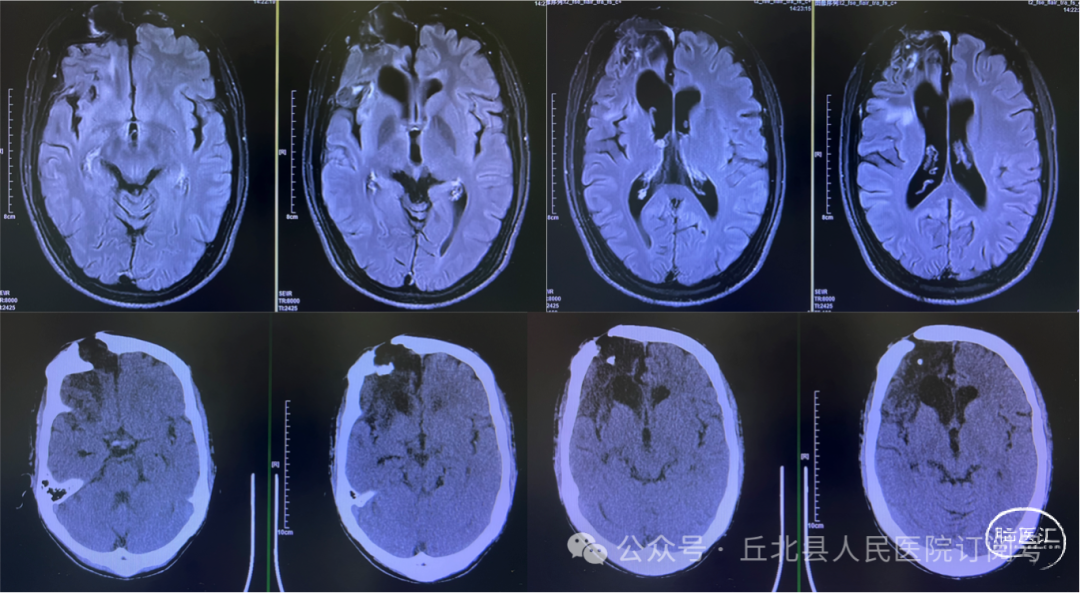

术后影像评估